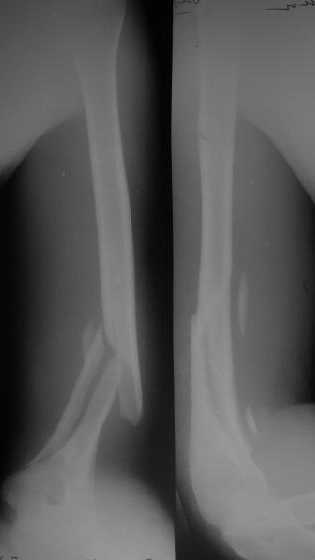

>антероградный - 30 процентов имеют боль в плече, связанную с повреждением ротаторной манжеты

Мы в последние годы все еще используем для переломов такой локализации эластичные титановые стержни (по мотивам ярославских разработок, Зверева-Ключевского). Такой стержень можно вводить не через сухожилие надостной мышцы, а дистальнее.

Снимки до, через 1 и 2 мес. после синтеза.